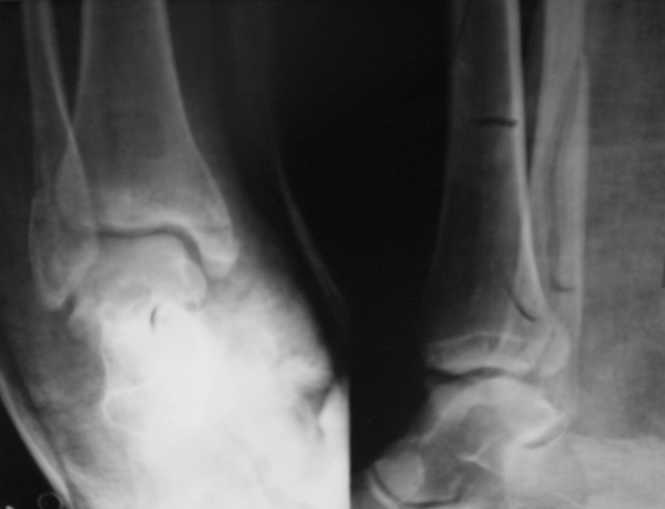

Re: Перелом лодыжек

послал Sergey Melasenko 19 Декабрь 2007, 01:37

Вот рентгенконтроль на 7-е сутки после репозиции.